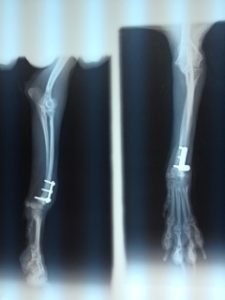

小型犬の橈尺骨骨折

2013.08.13